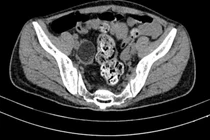

Qua thăm khám và kết quả siêu âm, bác sĩ nhận định nữ bệnh nhân có khối u buồng trứng bên phải, kích thước rất lớn (12 x 18cm) và chỉ định phẫu thuật cắt bỏ khối u.

Điều đặc biệt, khối u được xác định là u quái buồng trứng hiếm gặp bởi chứa nhiều tóc, móng và xương bên trong.